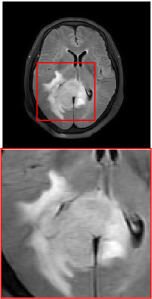

Figure 5 provides the qualitative comparison of the various methods on the four datasets at a scale of 4. The top, second, third, and bottom rows are the SR results under the FastMRI, clinical brain, clinical tumor and clinical pelvic datasets, respectively. The red boxes indicate the zoom-in region of complicated anatomical structures along with their corresponding error maps. Note that the brighter textures in the error maps, the lower the quality of the reconstructed images. As can be seen, compared to methods based on Transformers and CNNs, diffusion-based methods like DisC-Diff and DiffMSR (Ours) are capable of reconstructing high-realistic images with promising reconstruction metric scores (PSNR and SSIM). Nevertheless, while DisC-Diff can reconstruct high-precision MR images, it does not preserve the structure present in the original HR images, introducing some additional information that can affect medical diagnosis. In contrast, our method combines DM and PLWformer, which can preserve the original image’s structure while restoring high-frequency information.

In this section, we present more visual qualitative comparisons. Figures 8, 9, 10, and 11 show the reconstruction results of each method in FastMRI, clinical brain, clinical tumor, and clinical pelvic, respectively. As can be seen, although DisC-Diff can reconstruct MR images with high-frequency information, it fails to preserve the structure and content of the original Target HR image effectively, resulting in image distortion. In contrast, our proposed DiffMSR can restore high-frequency information while preserving the structure of the original HR image, indicating the effectiveness of the joint use of DM and PLWformer.